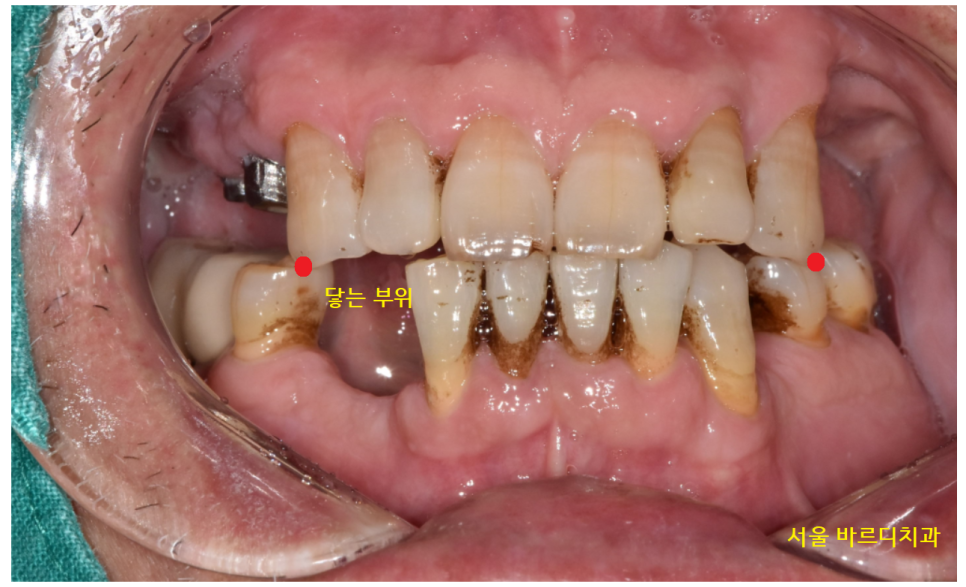

전반적으로 잇몸 뼈가 많이 내려가신 상태

위아래가 닿고 있는 부위가 2개뿐이라

식사가 어려우셨겠어요.

기존 치아 중에서도 문제가 많았습니다.